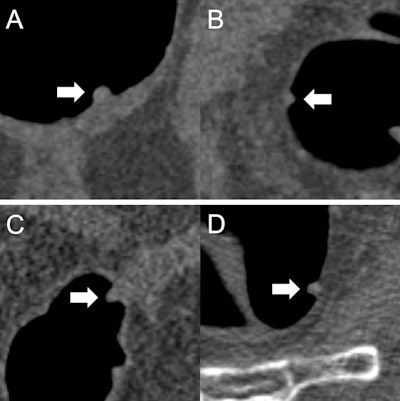

(A) A 9 mm tubular adenoma that was classified by all readers as "polypectomy: yes." The initial recommendation was confirmed based on the prediction "adenomatous" of the AI model. (B) A 6 mm hyperplastic polyp that was classified by all readers as "polypectomy: no." The initial recommendation was confirmed based on the prediction "nonadenomatous" of the AI model. (C) An 8 mm tubular adenoma that was classified by three readers as "polypectomy: no." The initial recommendation was corrected by all three readers based on the prediction "adenomatous" of the AI model. (D) A 7 mm hyperplastic polyp that was classified by two readers as "polypectomy: yes." The initial recommendation was corrected by both readers based on the prediction "nonadenomatous" of the AI model. All figures courtesy of Dr. Sergio Grosu et al and European Radiology.

The current lack of data on the impact of computer-aided classification of CT colonography-detected colorectal polyps on therapy management prompted the Munich group to evaluate the effect of AI-assisted differentiation of nonadenomatous and adenomatous colorectal polyps at CT colonography on radiologists' therapy management using a radiomics-based machine-learning model analyzing polyp characteristics beyond size and morphology.